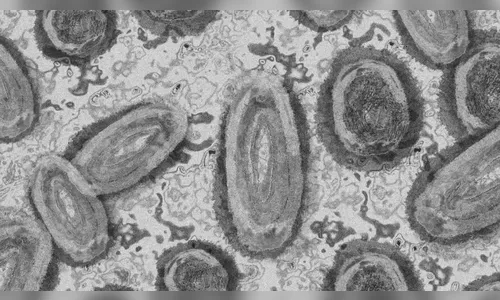

Os Estados Unidos registraram os primeiros casos de varíola dos macacos em crianças. A informação foi dada pela diretora do Centro para Controle e Prevenção de Doenças (CDC), Rochelle Walensky, em entrevista ao jornal Washington Post, na sexta-feira (22). São duas crianças infectadas, sendo que uma delas ainda é uma criança de colo, em casos não relacionados.